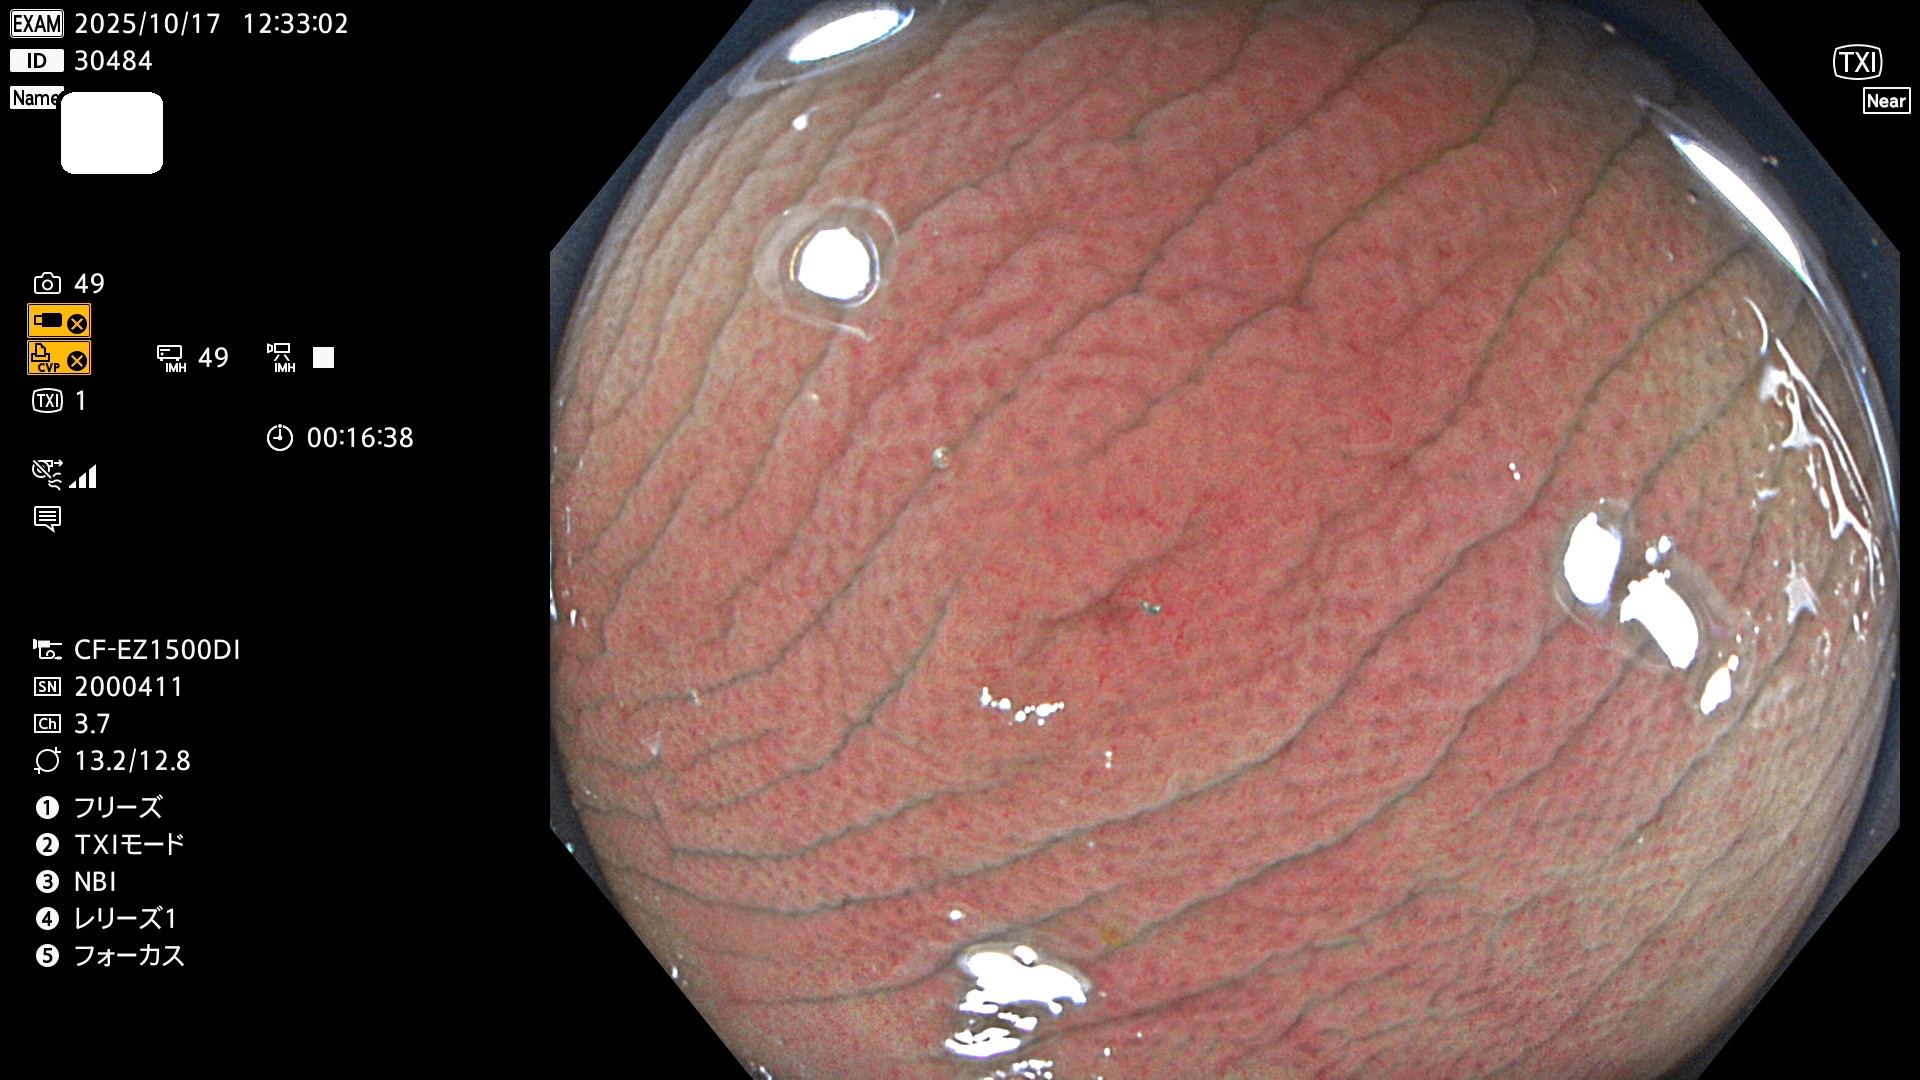

完全に平坦な物をUb、陥凹している物をUcと呼びます。Ubは認識が困難で、Ucはびらん(炎症)と紛らわしいために見落とされやすく、「内視鏡後・大腸癌」の原因になります。

専門的)Uc=De Novo癌? 内視鏡の解像度が低かった時代、このような説もありました。しかし今日の高精度内視鏡では良性の微小なUc型腺腫(APC遺伝子異常の腺腫)が日常的に見つかります。Ucこそが多段階発癌(Adenoma-Carcinoma Sequence)のMain Routeです。

毎週の検査(木・金・土・日)に発見されたUbとUc型・腺腫を、その週の日曜の夜にUPし1週間、提示します。

2025年10月16日〜10月19日の4日間(40件)2個 (Uc_ADR=2個/40人=5%)